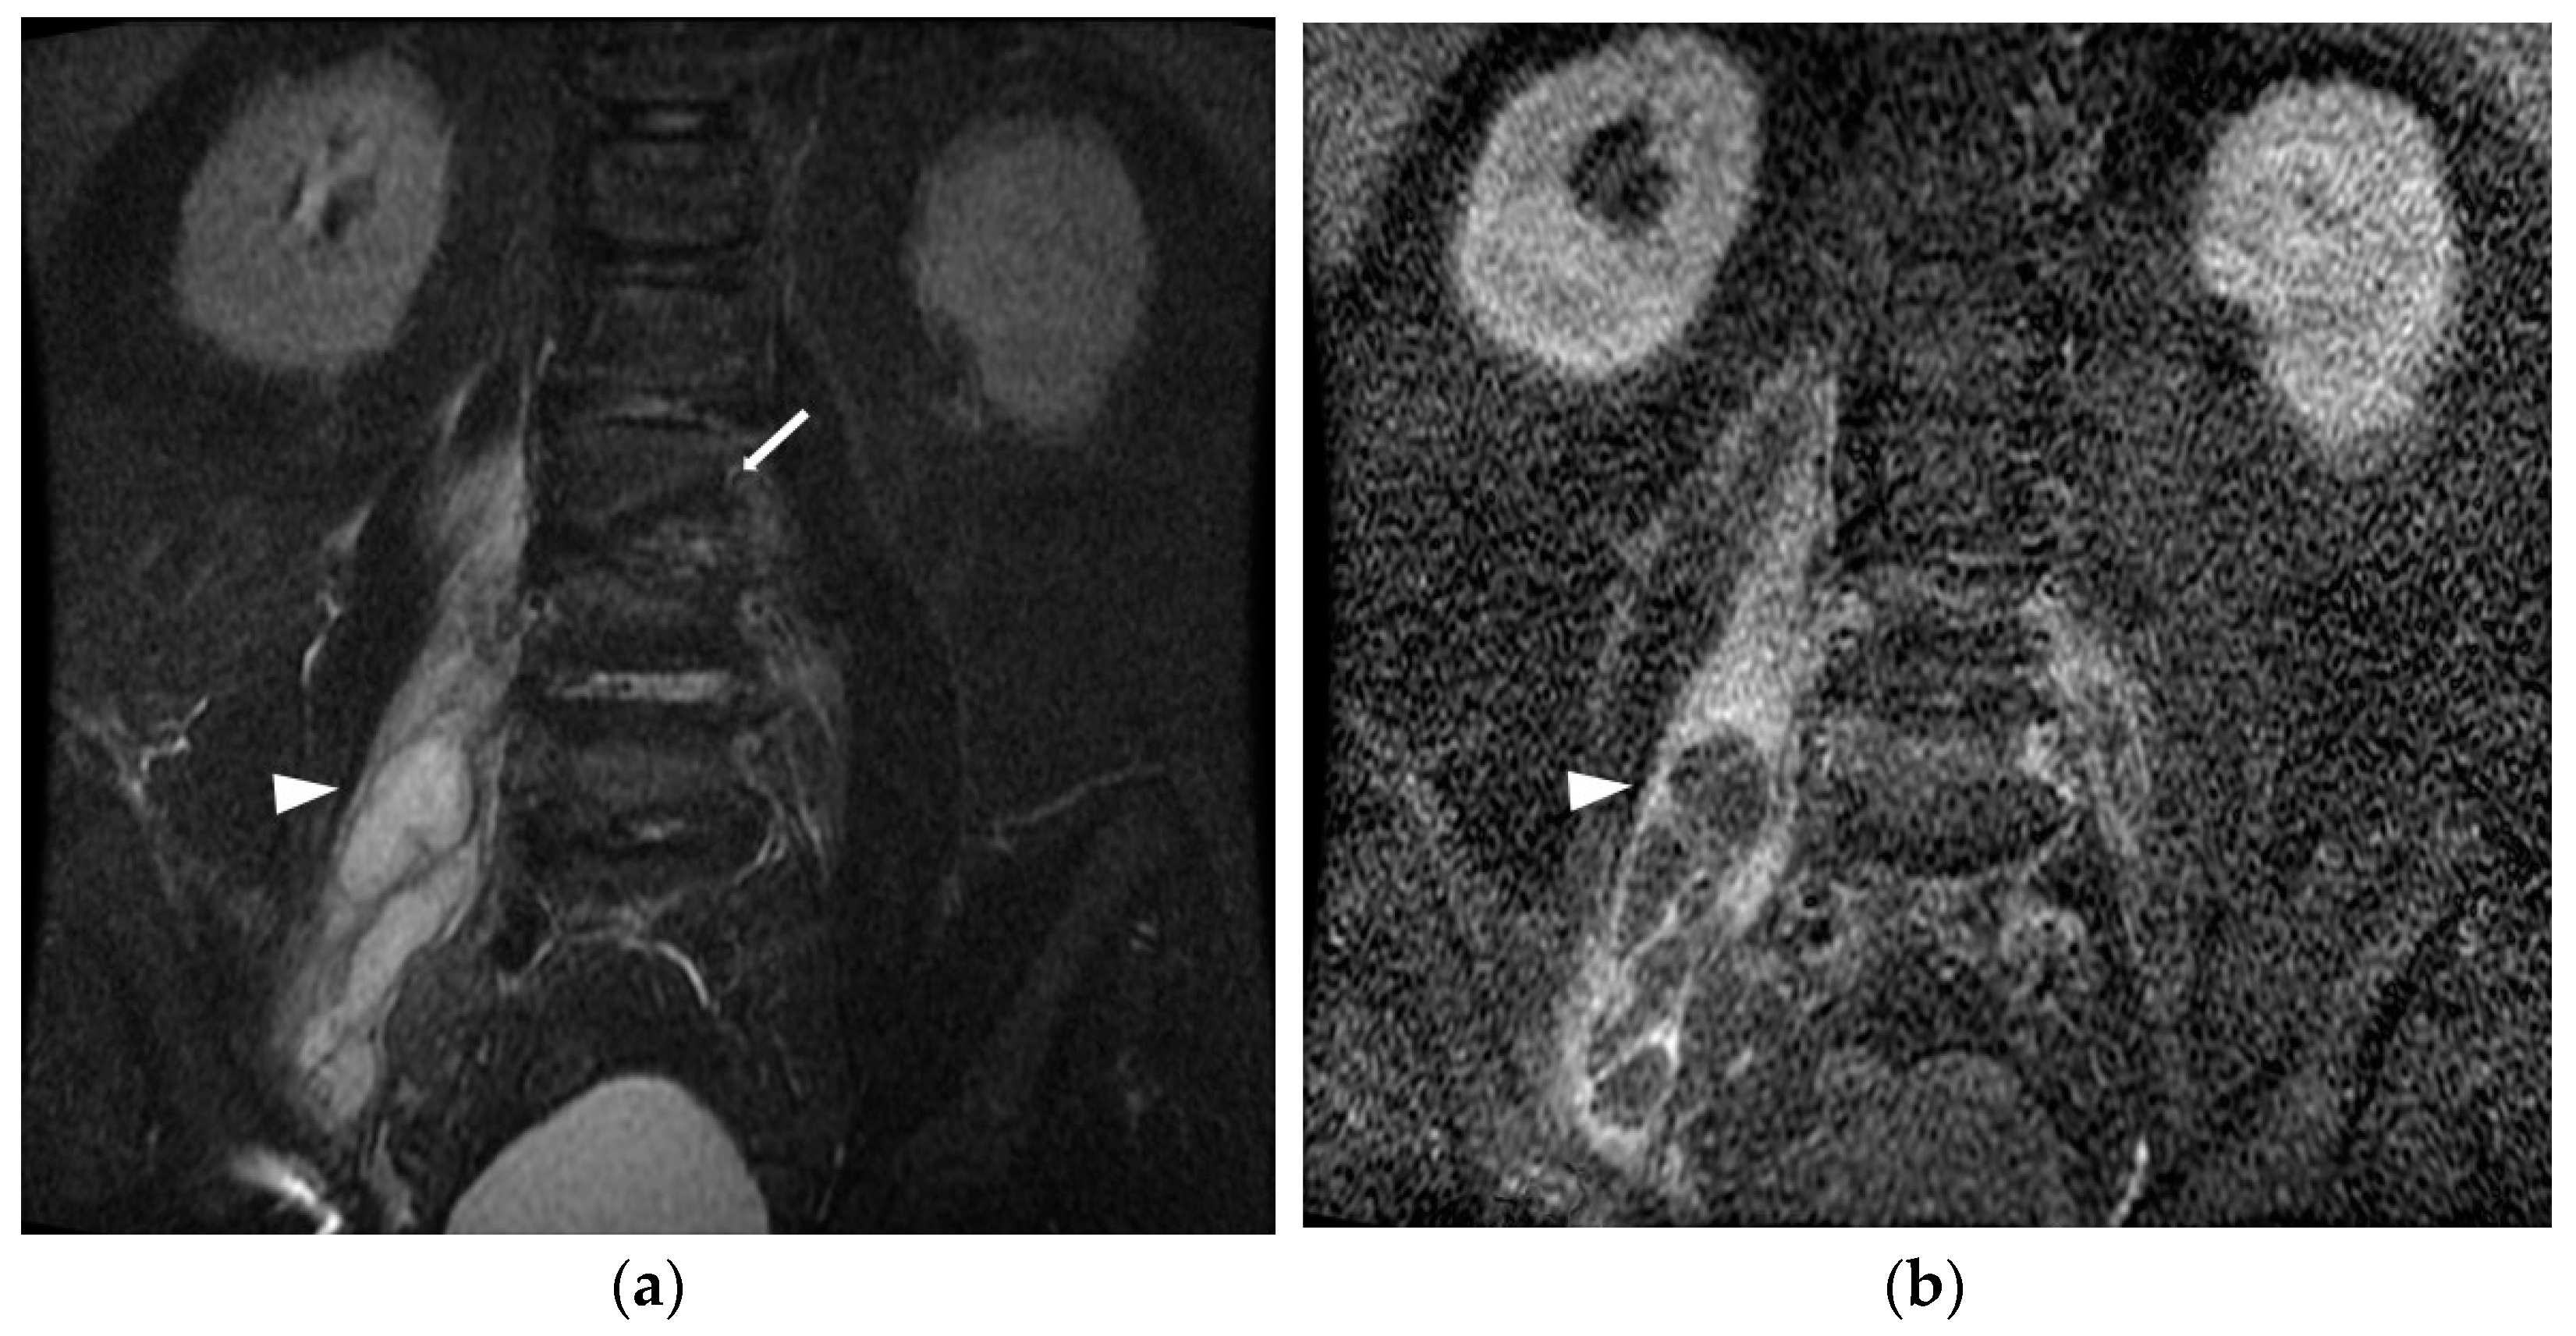

A diagnosis of iliopsoas abscess was made if the patient showed the clinical symptoms of iliopsoas abscess and met one of the following criteria. (1) One or more positive culture or gram stain on iliopsoas compartment aspiration or surgical specimens was detected; or (2) radiological findings—including evidence from computed tomography (CT) or magnetic resonance imaging (MRI)—revealed the presence of an iliopsoas abscess, which was consistent with the patient’s clinical presentation. The characteristics of an iliopsoas abscess in CT or MRI typically include: (1) enlargement of the involved muscle; (2) rim enhancement around the abscess with decreased density in the center; and (3) the presence of gas within the abscess, visible as an air–fluid interface or small pockets of air [1]. The images were reviewed by experienced radiologists to ensure accurate diagnosis of iliopsoas abscess (Figure 1).

Figure 1. Pyogenic spondylodiscitis complicating iliopsoas abscess in a 58-year-old male. (a) Magnetic resonance (MR) image of L-S spine of coronal short T1 inversion recovery (STIR) sequence showed cortical discontinuities and erosions of endplates (arrow) of L2, L3 vertebras with hyperintense of right iliopsoas muscle associated with intramuscular loculated fluid collections (arrowhead). (b) Contrast-enhanced MRI T1 weighted image (WI) with fat suppression showed prominent rim enhancement of loculated fluid collection in the right iliopsoas muscle, which was compatible with intramuscular abscess of the right iliopsoas muscle (arrowhead).